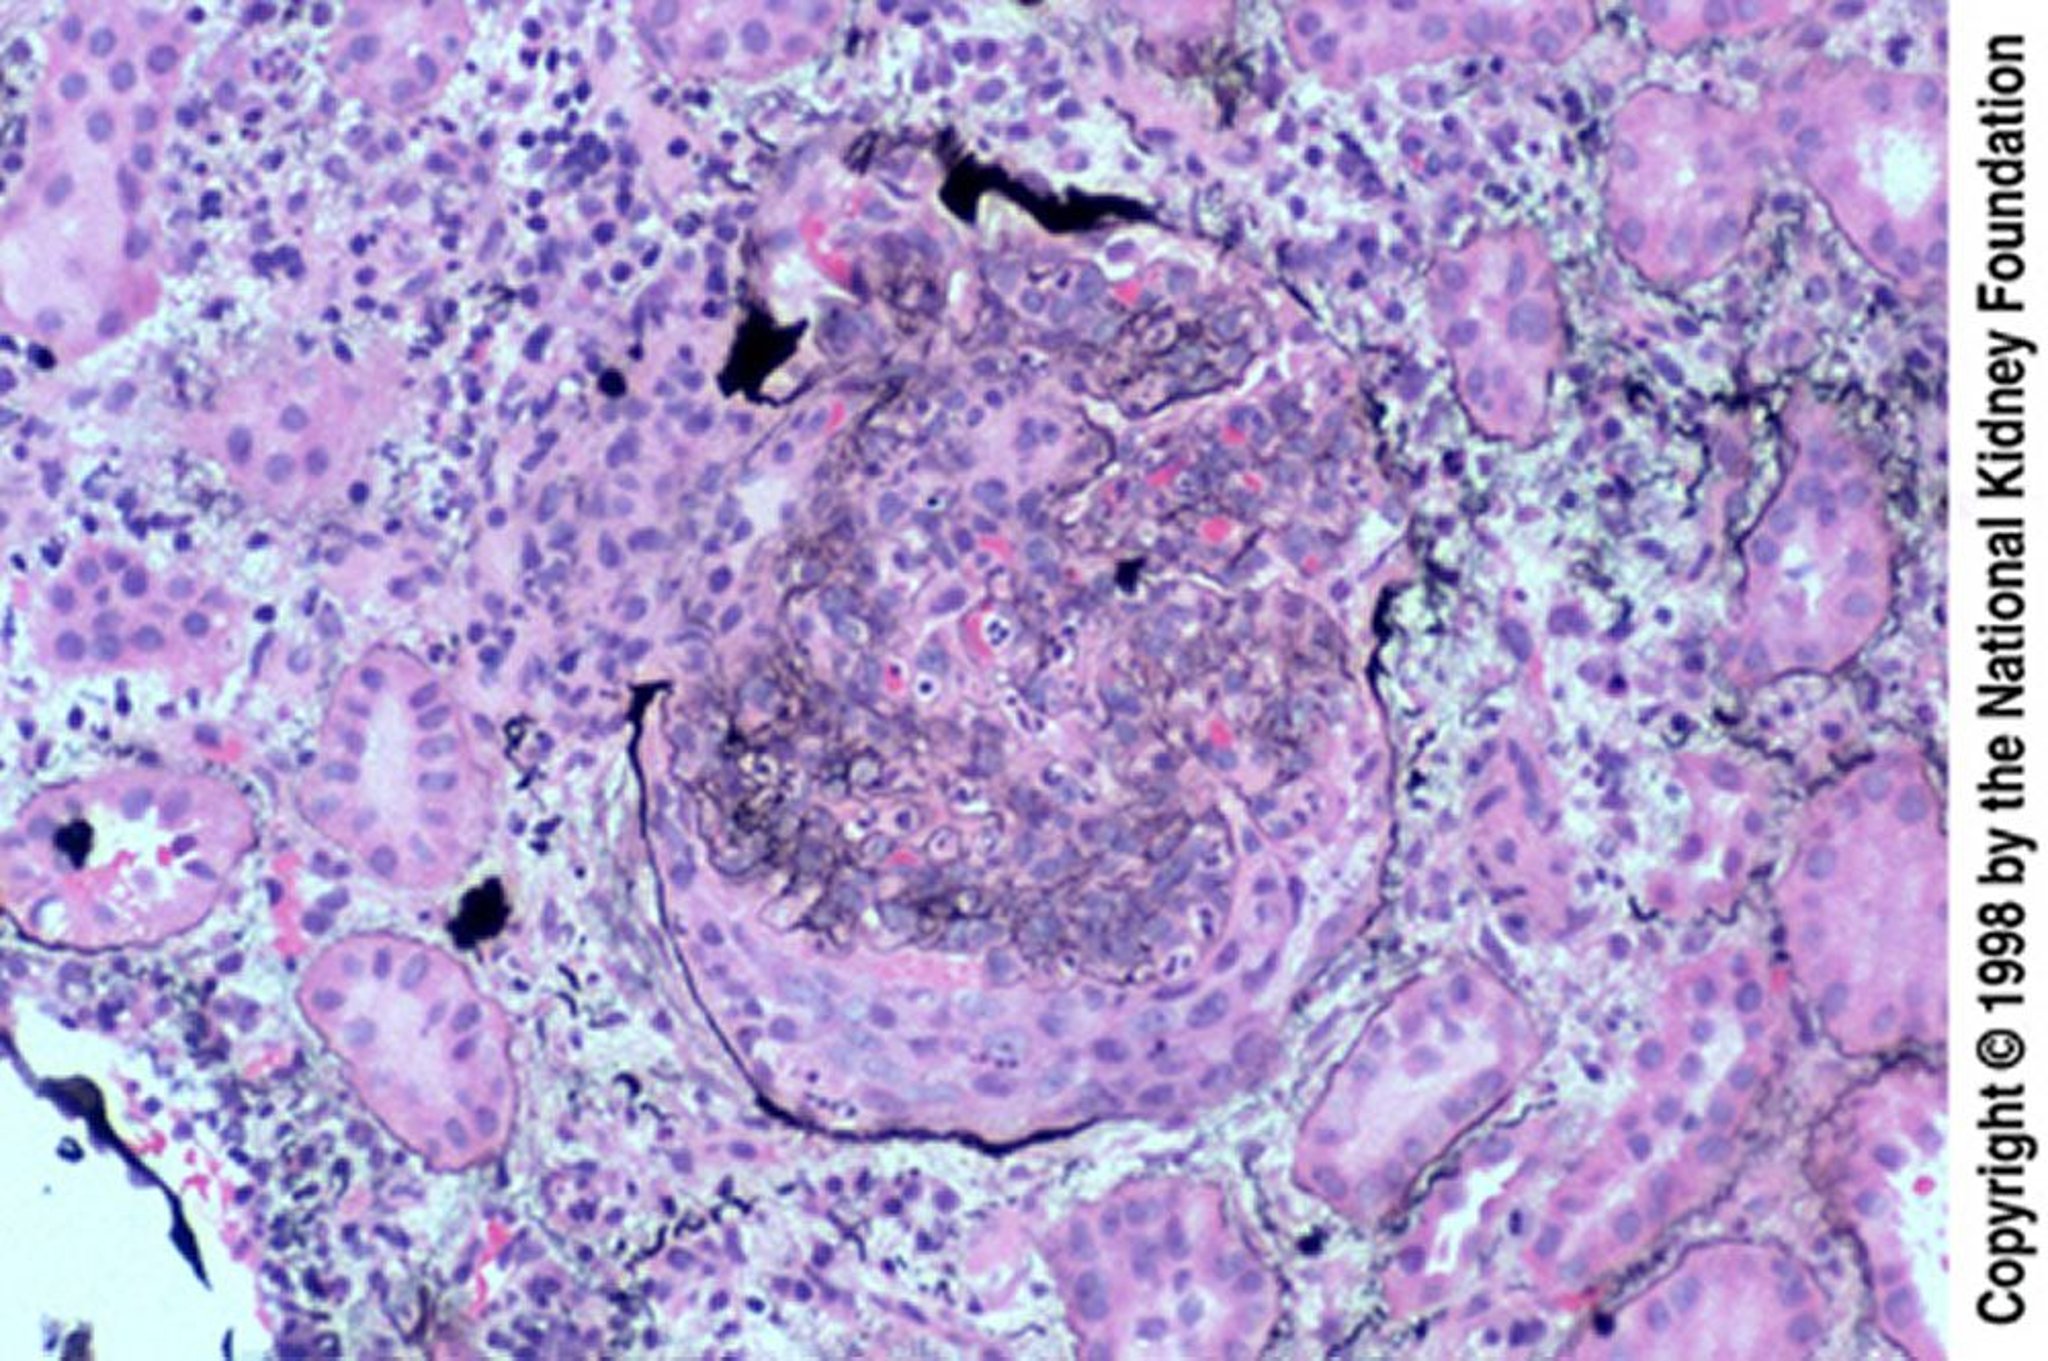

Glomerulonefritis posinfecciosa (medialunas epiteliales)

Las mediailunas epiteliales son especialmente comunes cuando la biopsia se obtiene en forma tardía, después de una respuesta fallida al tratamiento. La medialuna ha roto la cápsula de Bowman (tinción de Jones, ×200).

Image provided by Agnes Fogo, MD, and the American Journal of Kidney Diseases' Atlas of Renal Pathology (véase www.ajkd.org).